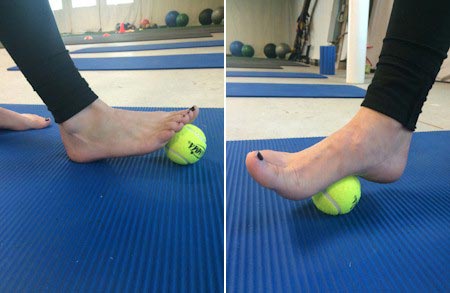

- کشش و غلتاندن کف پا